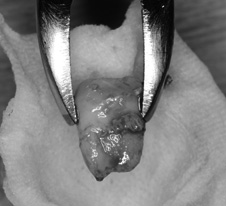

![]() |

| 抜歯した移植歯の親知らず 根の形態もよく、歯根膜も十分あり適応症です。 |